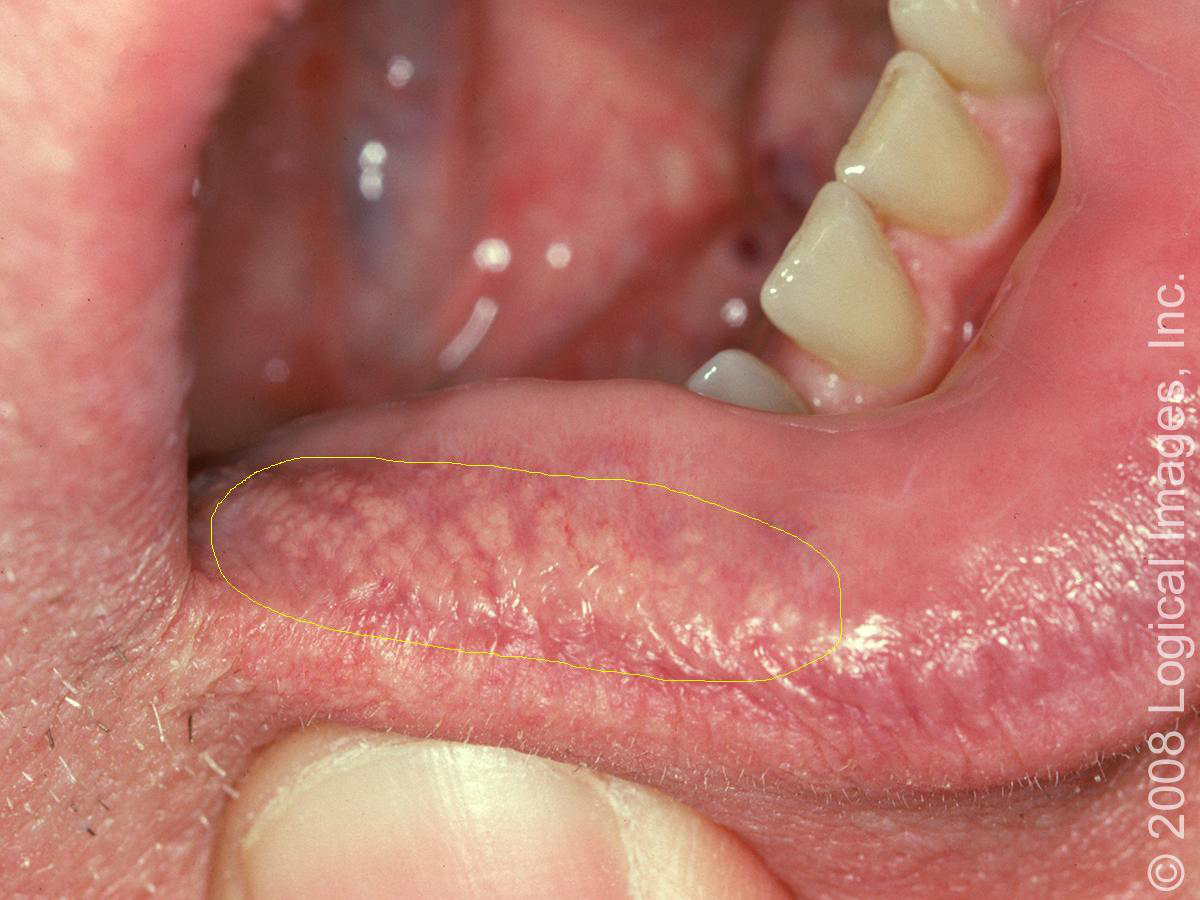

Hpv White Spots On Lips Pictures . They may occur in or around the genitals, anus, tongue, mouth, or lips. The red patches, known as erythroplasia, can appear on the gums, tongue, or mouth lining. White bumps on the lips can be harmless or indicate a viral or bacterial infection. What does hpv look like in your mouth? More research is necessary to determine exactly. Symptoms of hpv in the mouth can include small, hard, bumps. They will either be white or red. The white patches are known as leukoplakia that occur on the mucous membrane of the mouth, gums, or tongue. People often get it through having oral sex. Sometimes, hpv also causes warts. Changes to the coloration of your tongue will develop if you have oral cancer. Oral hpv occurs when a virus enters the body, usually through a cut or small tear inside of the mouth. A dermatologist or other doctor can diagnose the. Focal epithelial hyperplasia lesions usually resemble the normal mucosal color but may occasionally appear white and papillary (figure 2). Human papillomavirus (hpv) can affect the inside of the mouth, the tongue, and the lips.